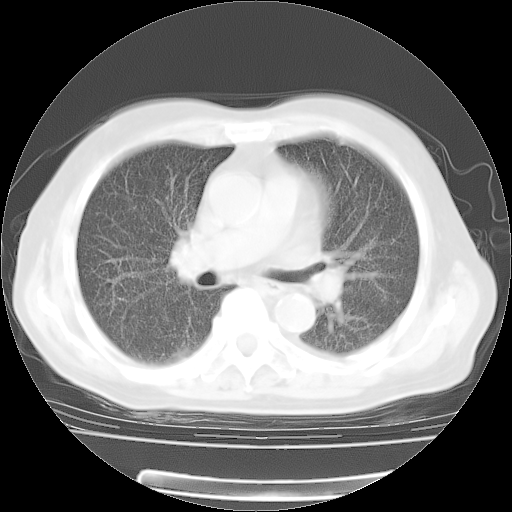

4月28日肺部CT

个人阅读4.14日肺部CT平扫:纵隔窗无异常,但肺窗示:双下肺内、后基底段有片絮状侵润影,部位以后基底段为著,以间质改变为主,呈急性肺泡炎征像,和首次住院影像学有相似之处。仅是个人读片,明日请相关专家再读片哈。其它建议同上。